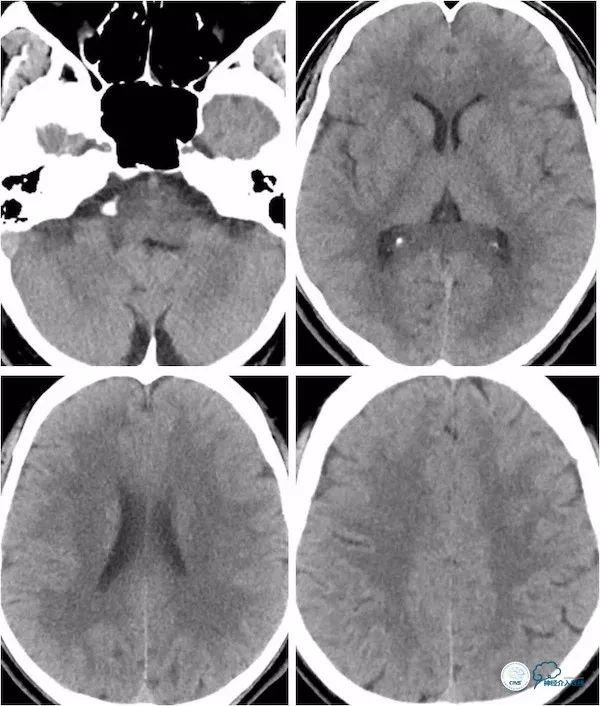

患者,男,49岁。主因“头晕、视物重影17天”入院。17天前患者无明显诱因突然出现头晕、视物重影,伴行走欠稳,就诊当地医院,行头颅CT平扫未见明显异常(图1)。

图1

头颅核磁检查:未见明显新近梗死(图2)。

图2